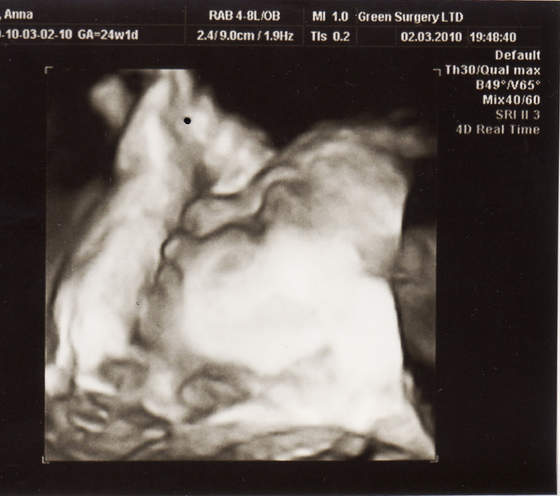

paula-śliczna duża babka i te murzyńskie usta ech!

ale lekarka mnie uspokoiłanadika wstydziosze z Natanka:-)Cudeńko z piękną wagąA co lekarz mówił na tą pępowinę?